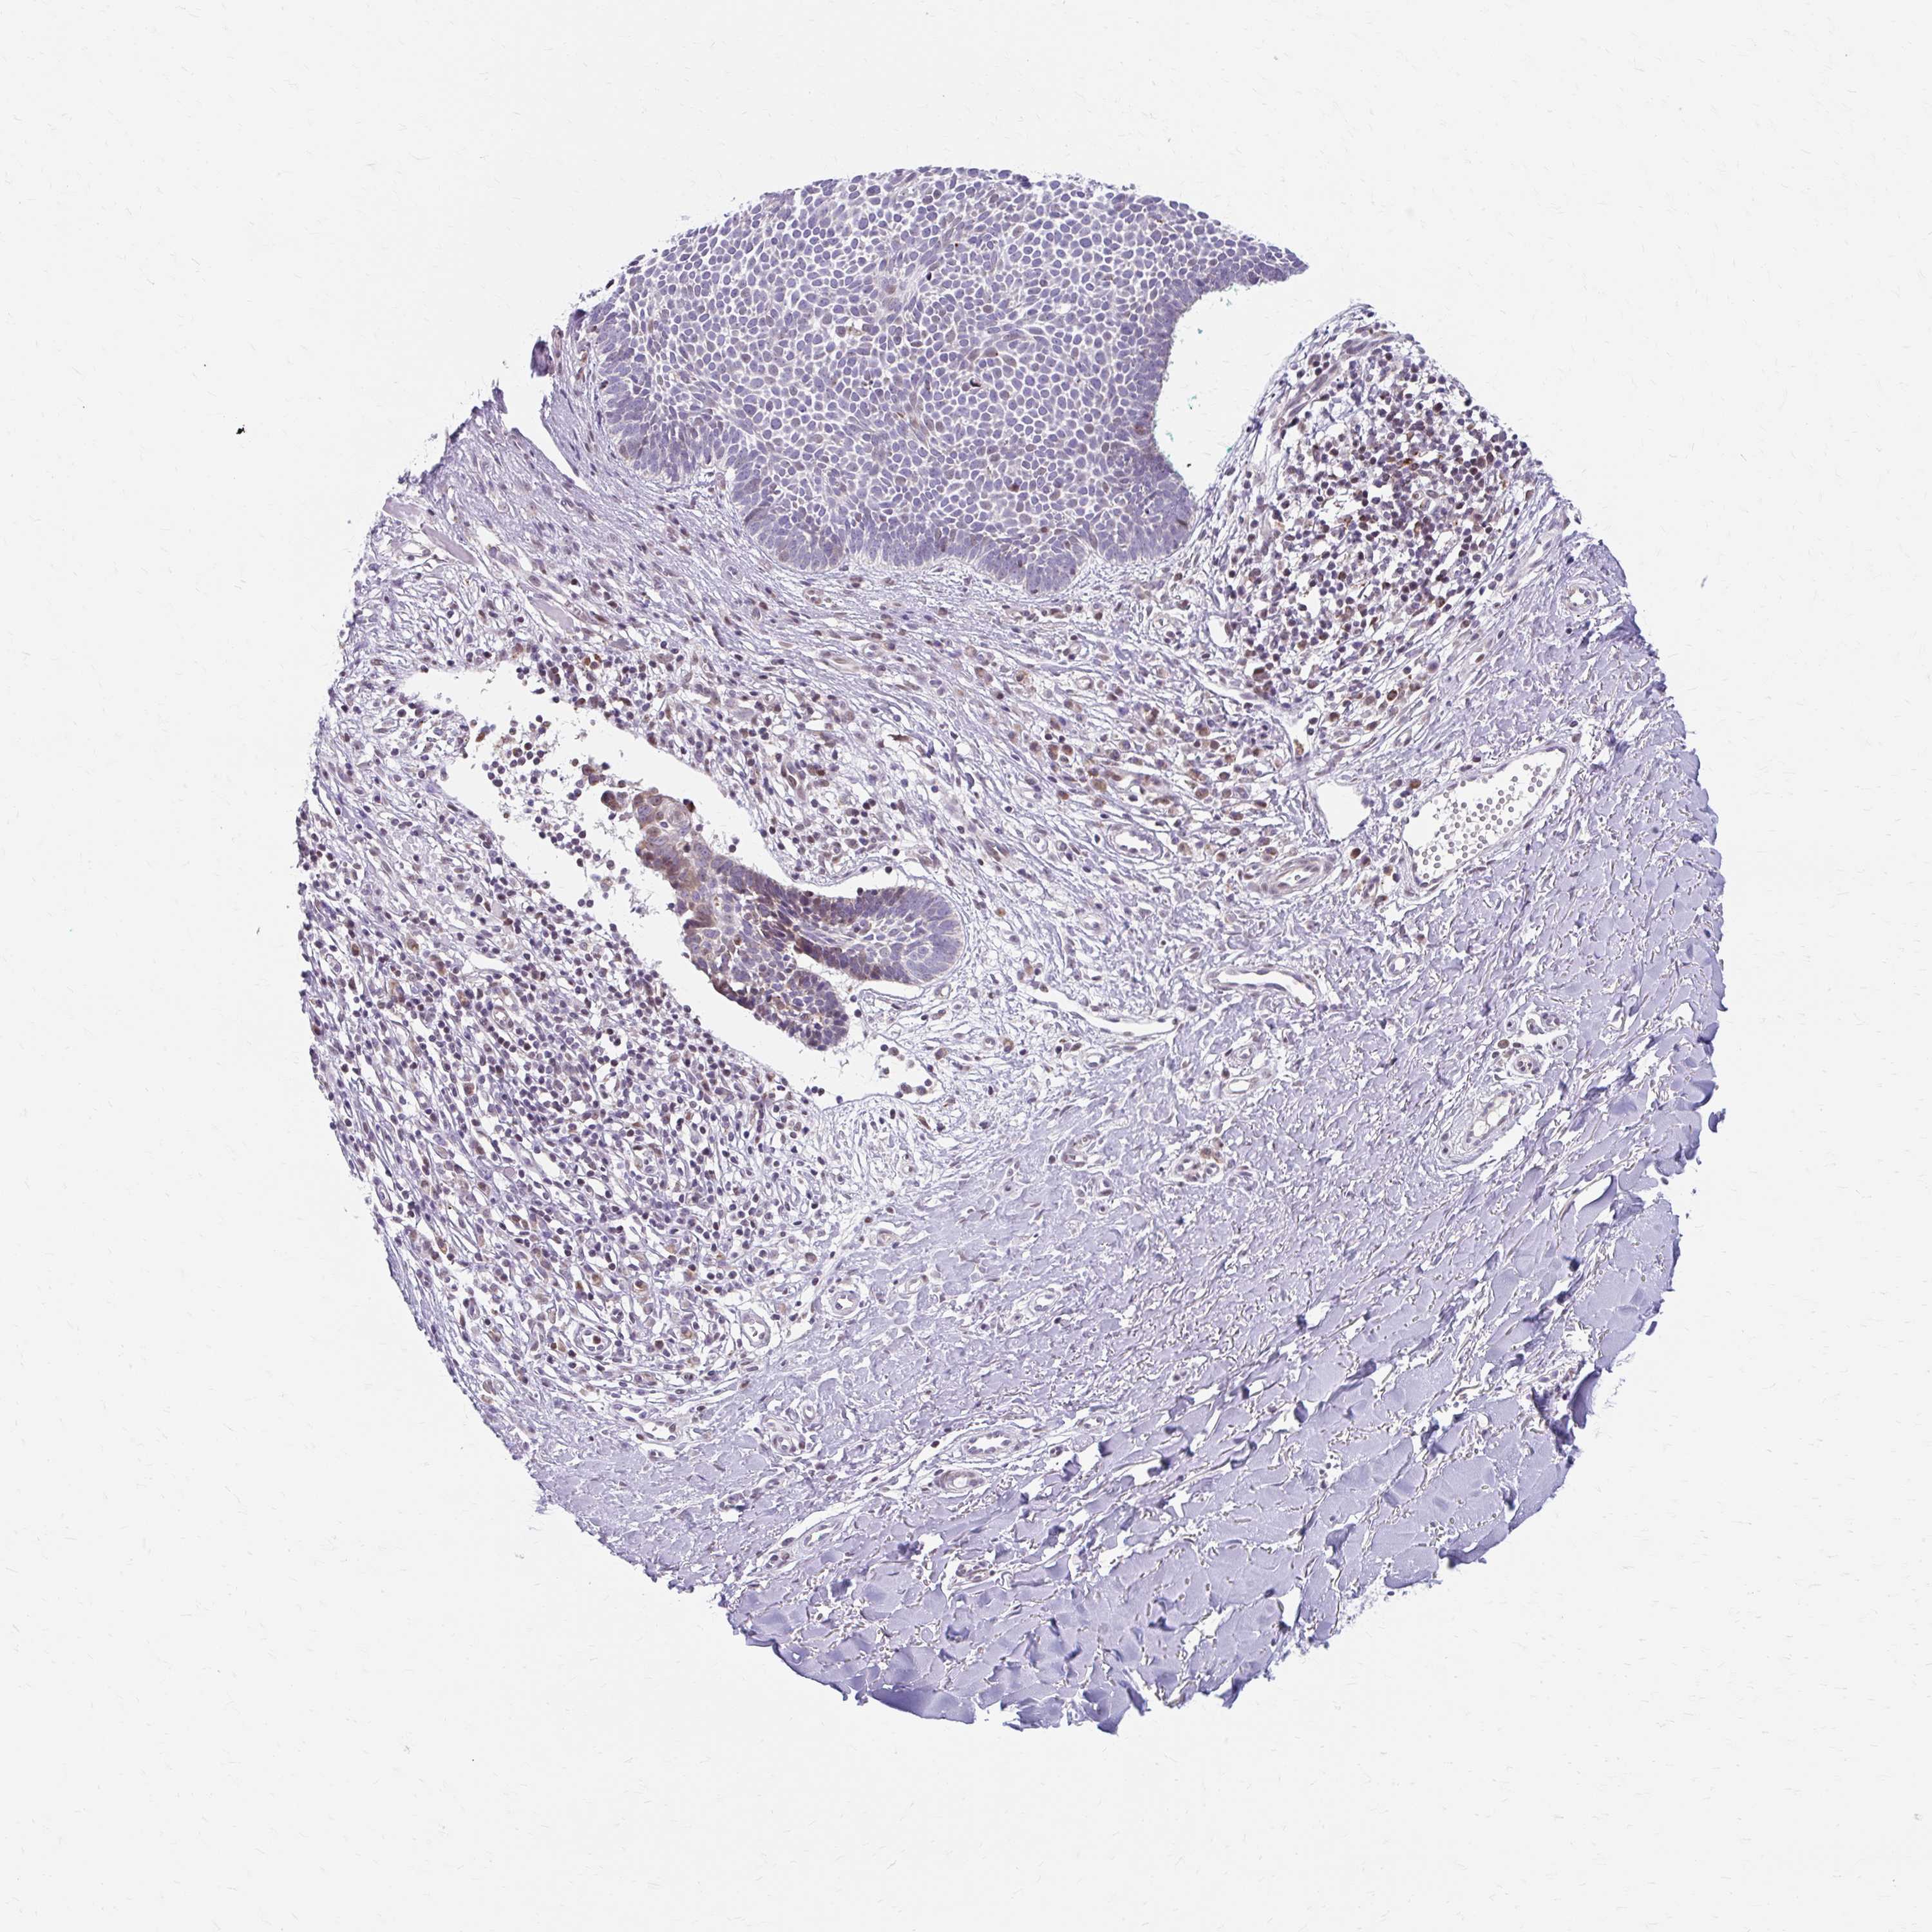

SKIN CANCER - Protein expressioni

A mouse-over function shows sample information and annotation data. Click on an image to view it in a full screen mode. Samples can be filtered based on level of antibody staining by selecting one or several of the following categories: high, medium, low and not detected. The assay and annotation is described here.

Antibody stainingi

Antibody staining in the annotated cell types in the current human tissue is reported as not detected, low, medium, or high, based on conventional immunohistochemistry profiling in selected tissues. This score is based on the combination of the staining intensity and fraction of stained cells.

Each image is clickable and will lead to virtual microscopy that enables deeper exploration of all samples and also displays staining intensity scores, fraction scores and subcellular localization as well as patient and tissue information for each sample.

Antibody HPA053851

Staining

High

Medium

Low

Not detected

Intensity

Strong

Moderate

Weak

Negative

Quantity

>75%

75%-25%

<25%

None

Location

Nuclear

Cytoplasmic/membranous

Cytoplasmic/membranous,nuclear

Basal cell carcinoma

Squamous cell carcinoma, NOS